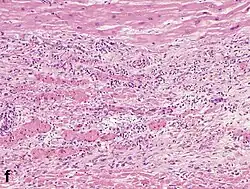

Although earlier changes can be discerned using electron microscopy, one of the earliest changes under a normal microscope are so-called wavy fibers.[23] Subsequently, the myocyte cytoplasm becomes more eosinophilic (pink) and the cells lose their transversal striations, with typical changes and eventually loss of the cell nucleus.[24] The interstitium at the margin of the infarcted area is initially infiltrated with neutrophils, then with lymphocytes and macrophages, who phagocytose ("eat") the myocyte debris. The necrotic area is surrounded and progressively invaded by granulation tissue, which will replace the infarct with a fibrous (collagenous) scar (which are typical steps in wound healing). The interstitial space (the space between cells outside of blood vessels) may be infiltrated with red blood cells.[22]

| Fibroblast and young collagen* | 5–10 days | 2–4 weeks | After 4 weeks; depends on size of infarction; |

| Dense fibrosis | 4 weeks | 2–3 months | No |